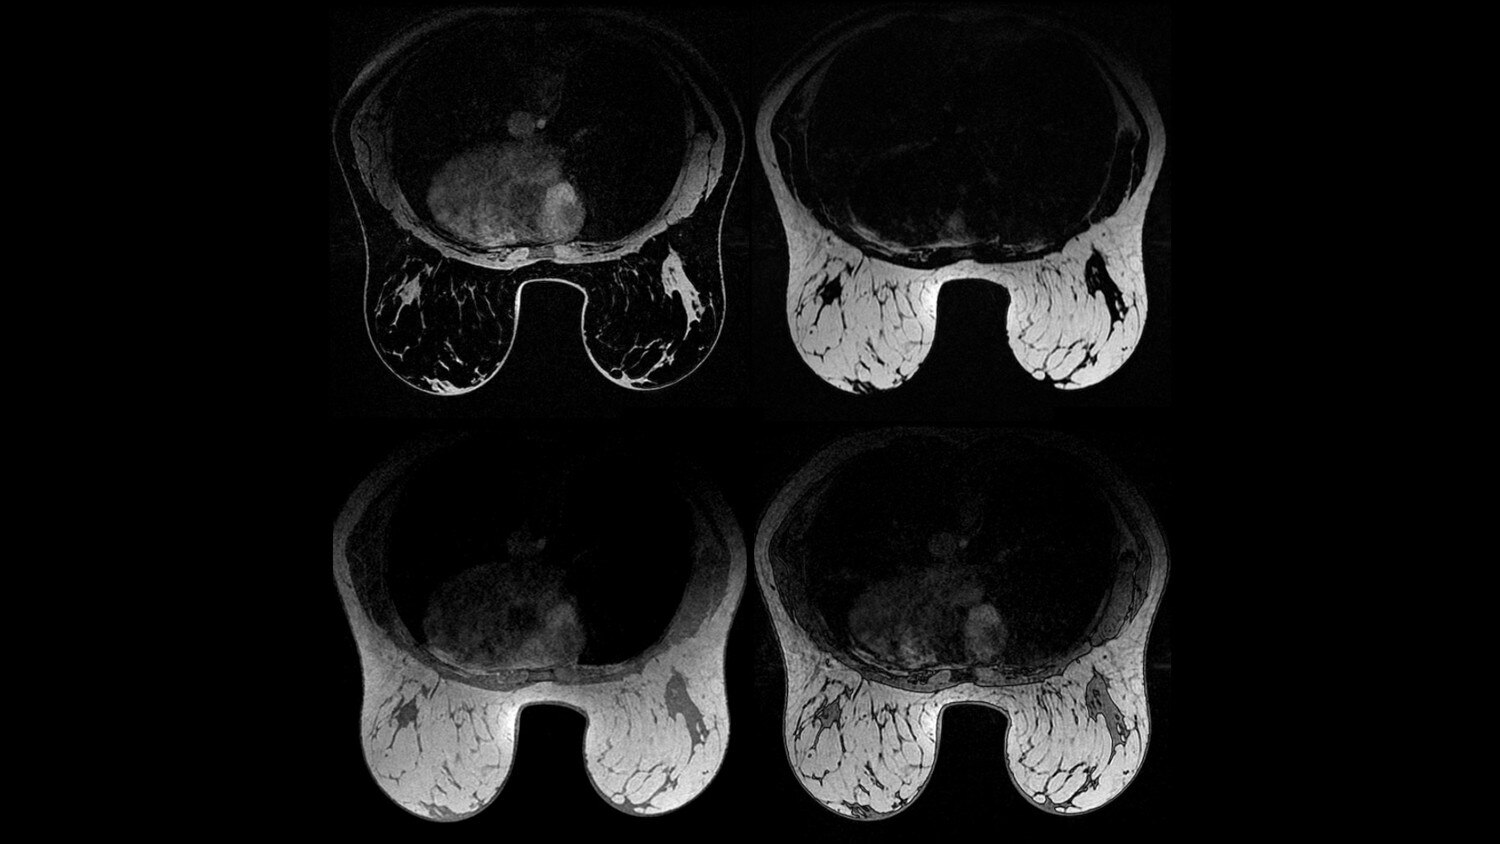

A large usable field of view is needed to properly image off-center anatomy such as a shoulder or hip. So the Discovery* MR750w features a 70 cm flared, open bore design with a large 50 x 50 x 50 cm field of view.

Gradients and RF body coils are water and air-cooled for optimum duty-cycle performance, short repetition time (TR) and echo time (TE), producing sharp and clear images.

Intuitive applications help clinicians utilize the full potential of 3.0T MR imaging.

GEM Anterior Array - A lightweight, flexible, thin and pre-formed array to embrace patients’ various sizes and shapes. With 54 cm of S/I coverage, the anterior array permits upper abdominal and pelvic imaging without repositioning the patient and supports parallel imaging in all 3 planes.